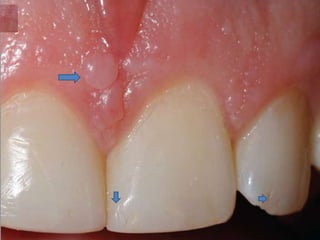

 Gingival fibromas

Gingival

fibromat

osis

• #19 Gingival fibromas and dental pitting